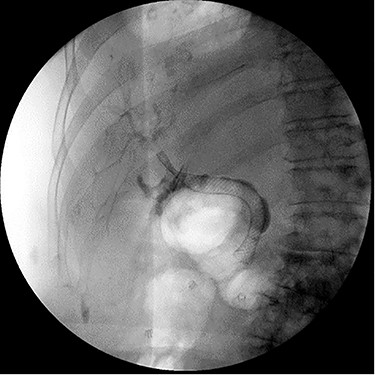

Repeat ERCP was performed and the CBD was easily traversed. Cholangiography demonstrated bile leakage within a well-developed sinus tract. A 10 x 80 mm fully covered metal Wallflex (Boston Scientific) stent was placed (Fig. 4).

ERCP demonstrating successful replacement of metal stent after explantation.